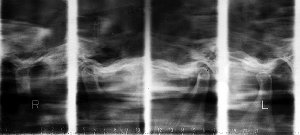

症例2 顎関節症(開口障害)